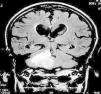

Masa cerebelosa en varón de 82 años

Cerebellar mass in a 82-year-old male